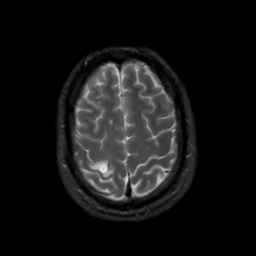

MR Study #6, March 17, 1991 -- Slice #41

[Home][Help][Clinical][Tour 1][Tour 2] Slice 41